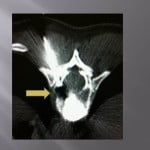

Vertebroplasty technique in the burst fracture of A2 type in the Magerl classification (split-burst fracture)

Vertebroplasty in the split-burst fracture is a delicate intervention for numerous reasons. The fracture separates the vertebral body into two parts with a possible recess of the posterior wall. This intervention stays in the limits of the indications of vertebroplasty, it must be decided in conjunction with the neurosurgical or orthopedic team.

Numerous publications show the efficacy of this procedure (amoretti, huet) and the small rate of complication. In our experience, the coupling of scopy and scanner is fundamental. The axial cuts allow for visualization of the extremities.

The progression of trocars is done successively by controlling the scanners and lateral scopies. We use 13 gauges trocars, the penetration is performed manually, we avoid using a surgical hammer to limit he risks of displacements of bone fragments. We **transfixions the fractured centre with the two trocars bilaterally and symmetrically. , their ends being located medially to limit lateral leaks.

The cement is injected at the level of the anterior fragment of the fracture at its paste phase, then the trocars are slowly withdrawn at the level of the fracture while injecting progressively the cement and create a cement bridge with the anterior fragment and the fracture trait. A scanner control verifies that the end of the trocars is located perfectly in the fracture. The cement is injected slowly in the cannula and pushes with the needle of the trocar.

The lateral scopy controls real time diffusion of the cement in the fracture. The axial scannographic cuts confirm the correct diffusion in the fracture and the absence of para-vertebral leaks. The trocars are progressively withdrawn while injecting cement in the cannula with a needle. Standing up is authorized the day after with wearing corset. The clinical and radiological follow up is rigorous to avoid detecting all neurological sign of compression and appreciate the vertebral consolidation.